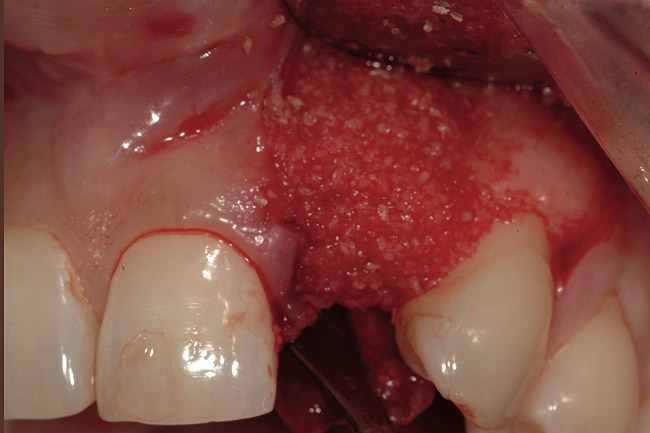

Figure 4   Extraction socket and ridge defect augmented with particulate freeze-dried bone allograft (FDBA) saturated with rhPDGF.

Figure 4

A 34-year-old woman presented with a chief complaint of mild discomfort and swelling associated with the maxillary left lateral incisor. The patient reported a history of root canal therapy and crown performed approximately 10 years earlier. Findings from the clinical examination revealed a localized buccal gingival swelling at the level of the mucogingival junction distal to the lateral incisor, with a 9-mm probing depth on the direct facial of the tooth (Figure 1 ). Observations from the radiographic examination demonstrated a periradicular radiolucency but suggested normal interdental bone levels (Figure 2 ). Surgical exposure following flap elevation exposed a 10-mm dehiscence defect of the buccal plate (Figure 3 ), which was consistent with a vertical root fracture and hopeless prognosis. The lateral incisor was extracted to minimize the loss of alveolar bone and this was followed by thorough degranulation of the socket. Particulate FDBA saturated with rhPDGF-BB for 10 minutes was then applied to augment the deficient ridge in preparation for future implant placement (Figure 4 ). The extraction site was developed to approximate the contours of the adjacent alveolar ridge. Then, a resorbable collagen membrane (Bio-Gide®, Osteohealth) was placed over the graft to facilitate graft containment and maintenance of desired alveolar contours (Figure 5 ). Placement of the membrane without disruption or displacement of the graft during completion of the surgical procedure and suturing is critical to ensure clot formation that will support bone formation.